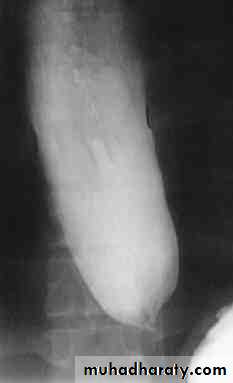

• Ba. swallow :

• 1-Constant narrowing.

• 2- Long length (lower third).

• 3-Smooth and regular.

• 4-Mild proximal dilatation.

• 5-No shouldering sign.

• 6-Smooth tapering

• ( funnel shape).